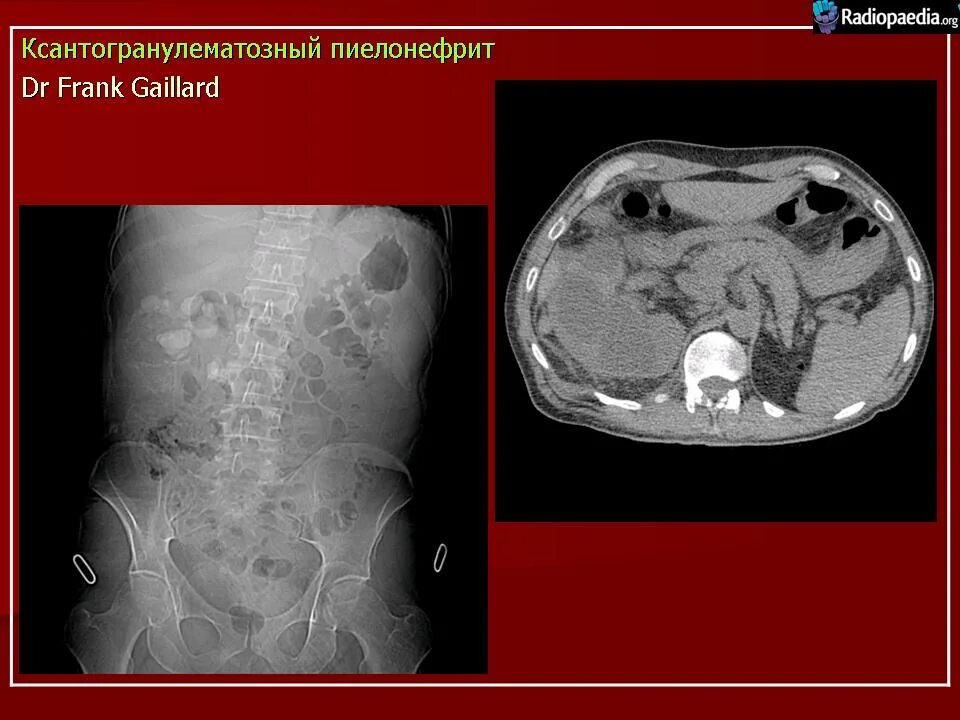

Пиелонефрит кт